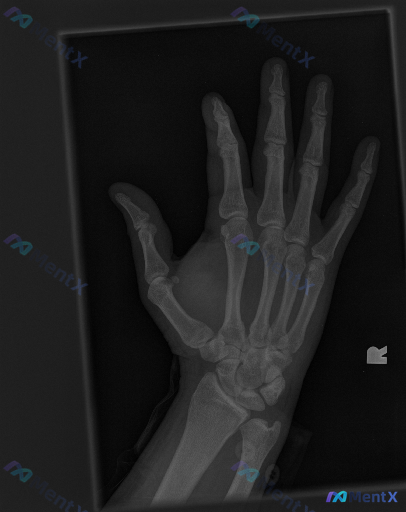

看到一份右手斜位X光片的读片资料,先把影像部分放出来: 影像所见(摘要): - 掌骨、指骨、腕骨形态完整,骨皮质连续,未见明确骨折线、骨膜反应或骨质破坏 - 腕掌、掌指、指间关节对位正常,关节面光滑,间隙未见明显狭窄/增宽 - 骨密度均匀,软组织轮廓正常,未见明显肿胀或高密度异物 影像结论: 在当前...

整理到一份右侧手部斜位X光片的影像资料与分析思路,想和大家讨论一下这类“影像看似正常,但可能有问题”的情况。 影像基础信息 - 投照体位:右侧手部斜位 - 显影质量:指骨、掌骨、腕骨结构显示清晰,曝光条件适中,骨皮质边缘与骨小梁均可分辨 直接影像学观察 - 骨皮质:逐一观察各手指及掌骨,未见明确中断...

整理到一份影像讨论资料,有点意思: 前提是:临床明确提示“存在异常”,但这份右手斜位X光的“基础版报告”写着—— - 骨皮质连续,未见明显骨折线/脱位 - 骨质密度、骨小梁大致正常 - 关节间隙尚可,无明显骨赘/侵蚀 - 软组织边界清,无广泛肿胀/气肿 但结合“存在异常”的这个大前提,再看同一张片子...